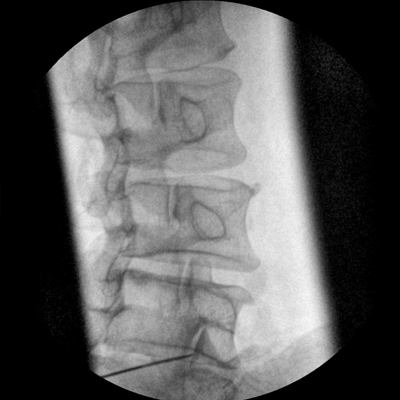

四維電動(dòng)運(yùn)動(dòng)控制,平滑定位,使得復(fù)雜角度快速實(shí)現(xiàn)。

專(zhuān)業(yè)的圖像處理系統(tǒng),為您提供高分辨率、高灰階圖像。